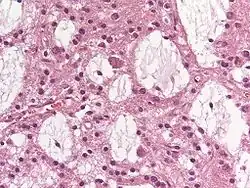

Obraz histologiczny

Histologicznie stwierdza się obecność mnogich guzków ograniczonych do kory mózgowej, zbudowanych z komórek przypominających oligodendrocyty (ang. oligodendrocyte-like cells, OGC).